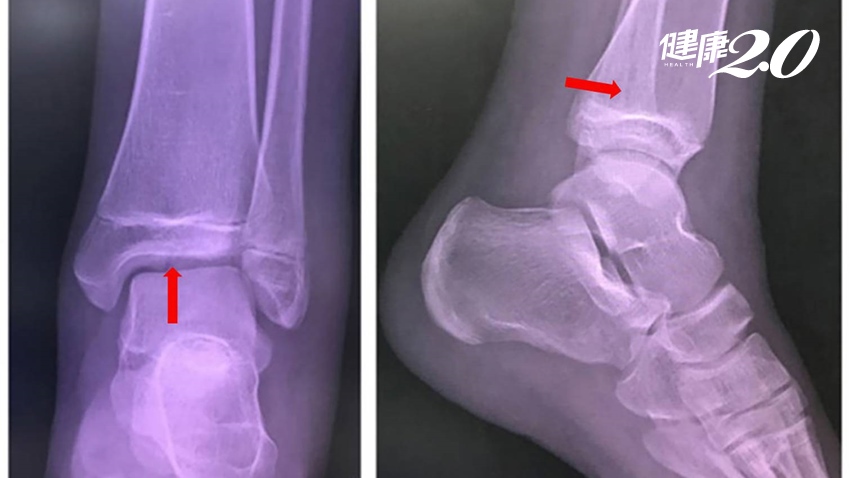

像張小妹妹這樣的骨折其實是很容易被忽略,在一般的X光上並不明顯,但在腳踝的電腦斷層上卻可以清楚看到複雜的骨折情形,這種情況稱之為踝關節遠端脛骨三平面型骨折 (Triplane fracture) 。

▲踝關節遠端脛骨三平面型骨折在X光上是無法看清楚。

在青少年踝關節骨折中遠端脛骨三平面型骨折約佔5-15%,好發年齡在10-17歲青少年,且男性較女性常見。臨床上的症狀,包括腫、痛及無法負重踩地,甚至是變形。由於這種三平面型骨折是貫穿過遠端脛骨的生長板,故可能造成骨頭的生長停滯,依文獻統計其發生率約為7-21%。

需長期追蹤避免長短腳或變形

此外,遠端脛骨生長板對下肢長度佔了15-20%的影響,因此這是青少年腳踝受傷時需要特別注意的一種骨折。在骨折固定治療之後,也需要持續追蹤是否發生因生長板生長停滯導致的長短腿及變形等後遺症。除此之外,遠端脛骨三平面型骨折也可能同時合併腓骨骨折(約50%)以及同側脛骨骨幹骨折,同樣是不可忽視的問題。